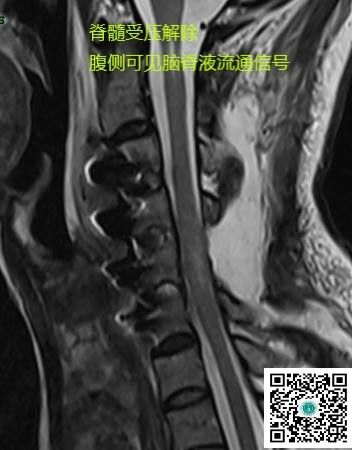

经后路切除椎管及椎间孔肿瘤,给肿瘤“除根”,为脊髓“减负”。

手术后一周,患者右上肢和双下肢肌力均恢复至5级,左上肢肌力4级,生活质量较术前显著改善。

术后CT见颈椎曲度和椎体间高度恢复满意。